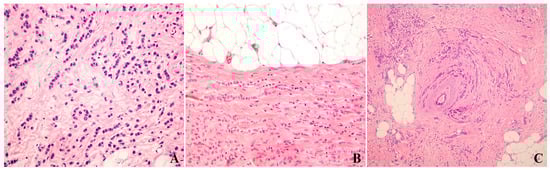

3.1. Classic Invasive Lobular Carcinoma

3.2. Histologic Variants of Invasive Lobular Carcinoma

3.3. Suboptimal Accuracy of Pathologic Classification of Invasive Lobular Carcinoma